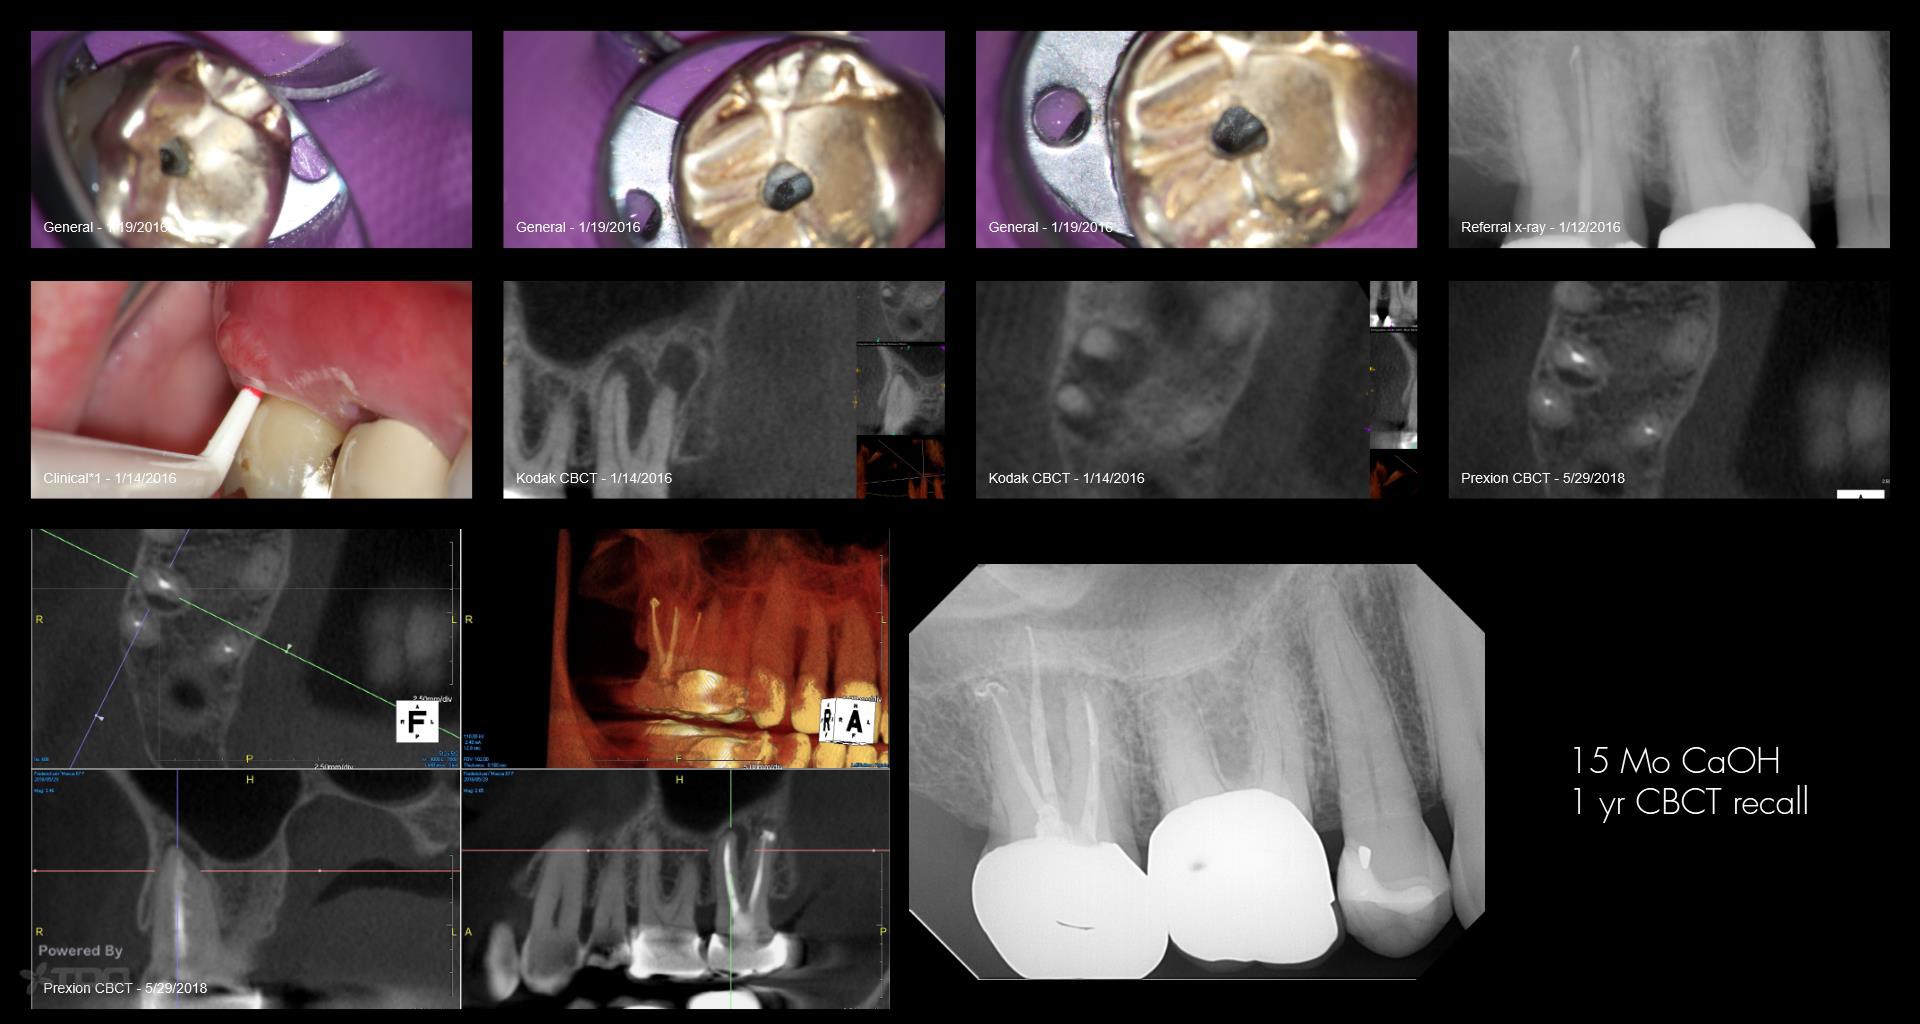

15 mo CaOH

Gary Carr

May 29, 2018